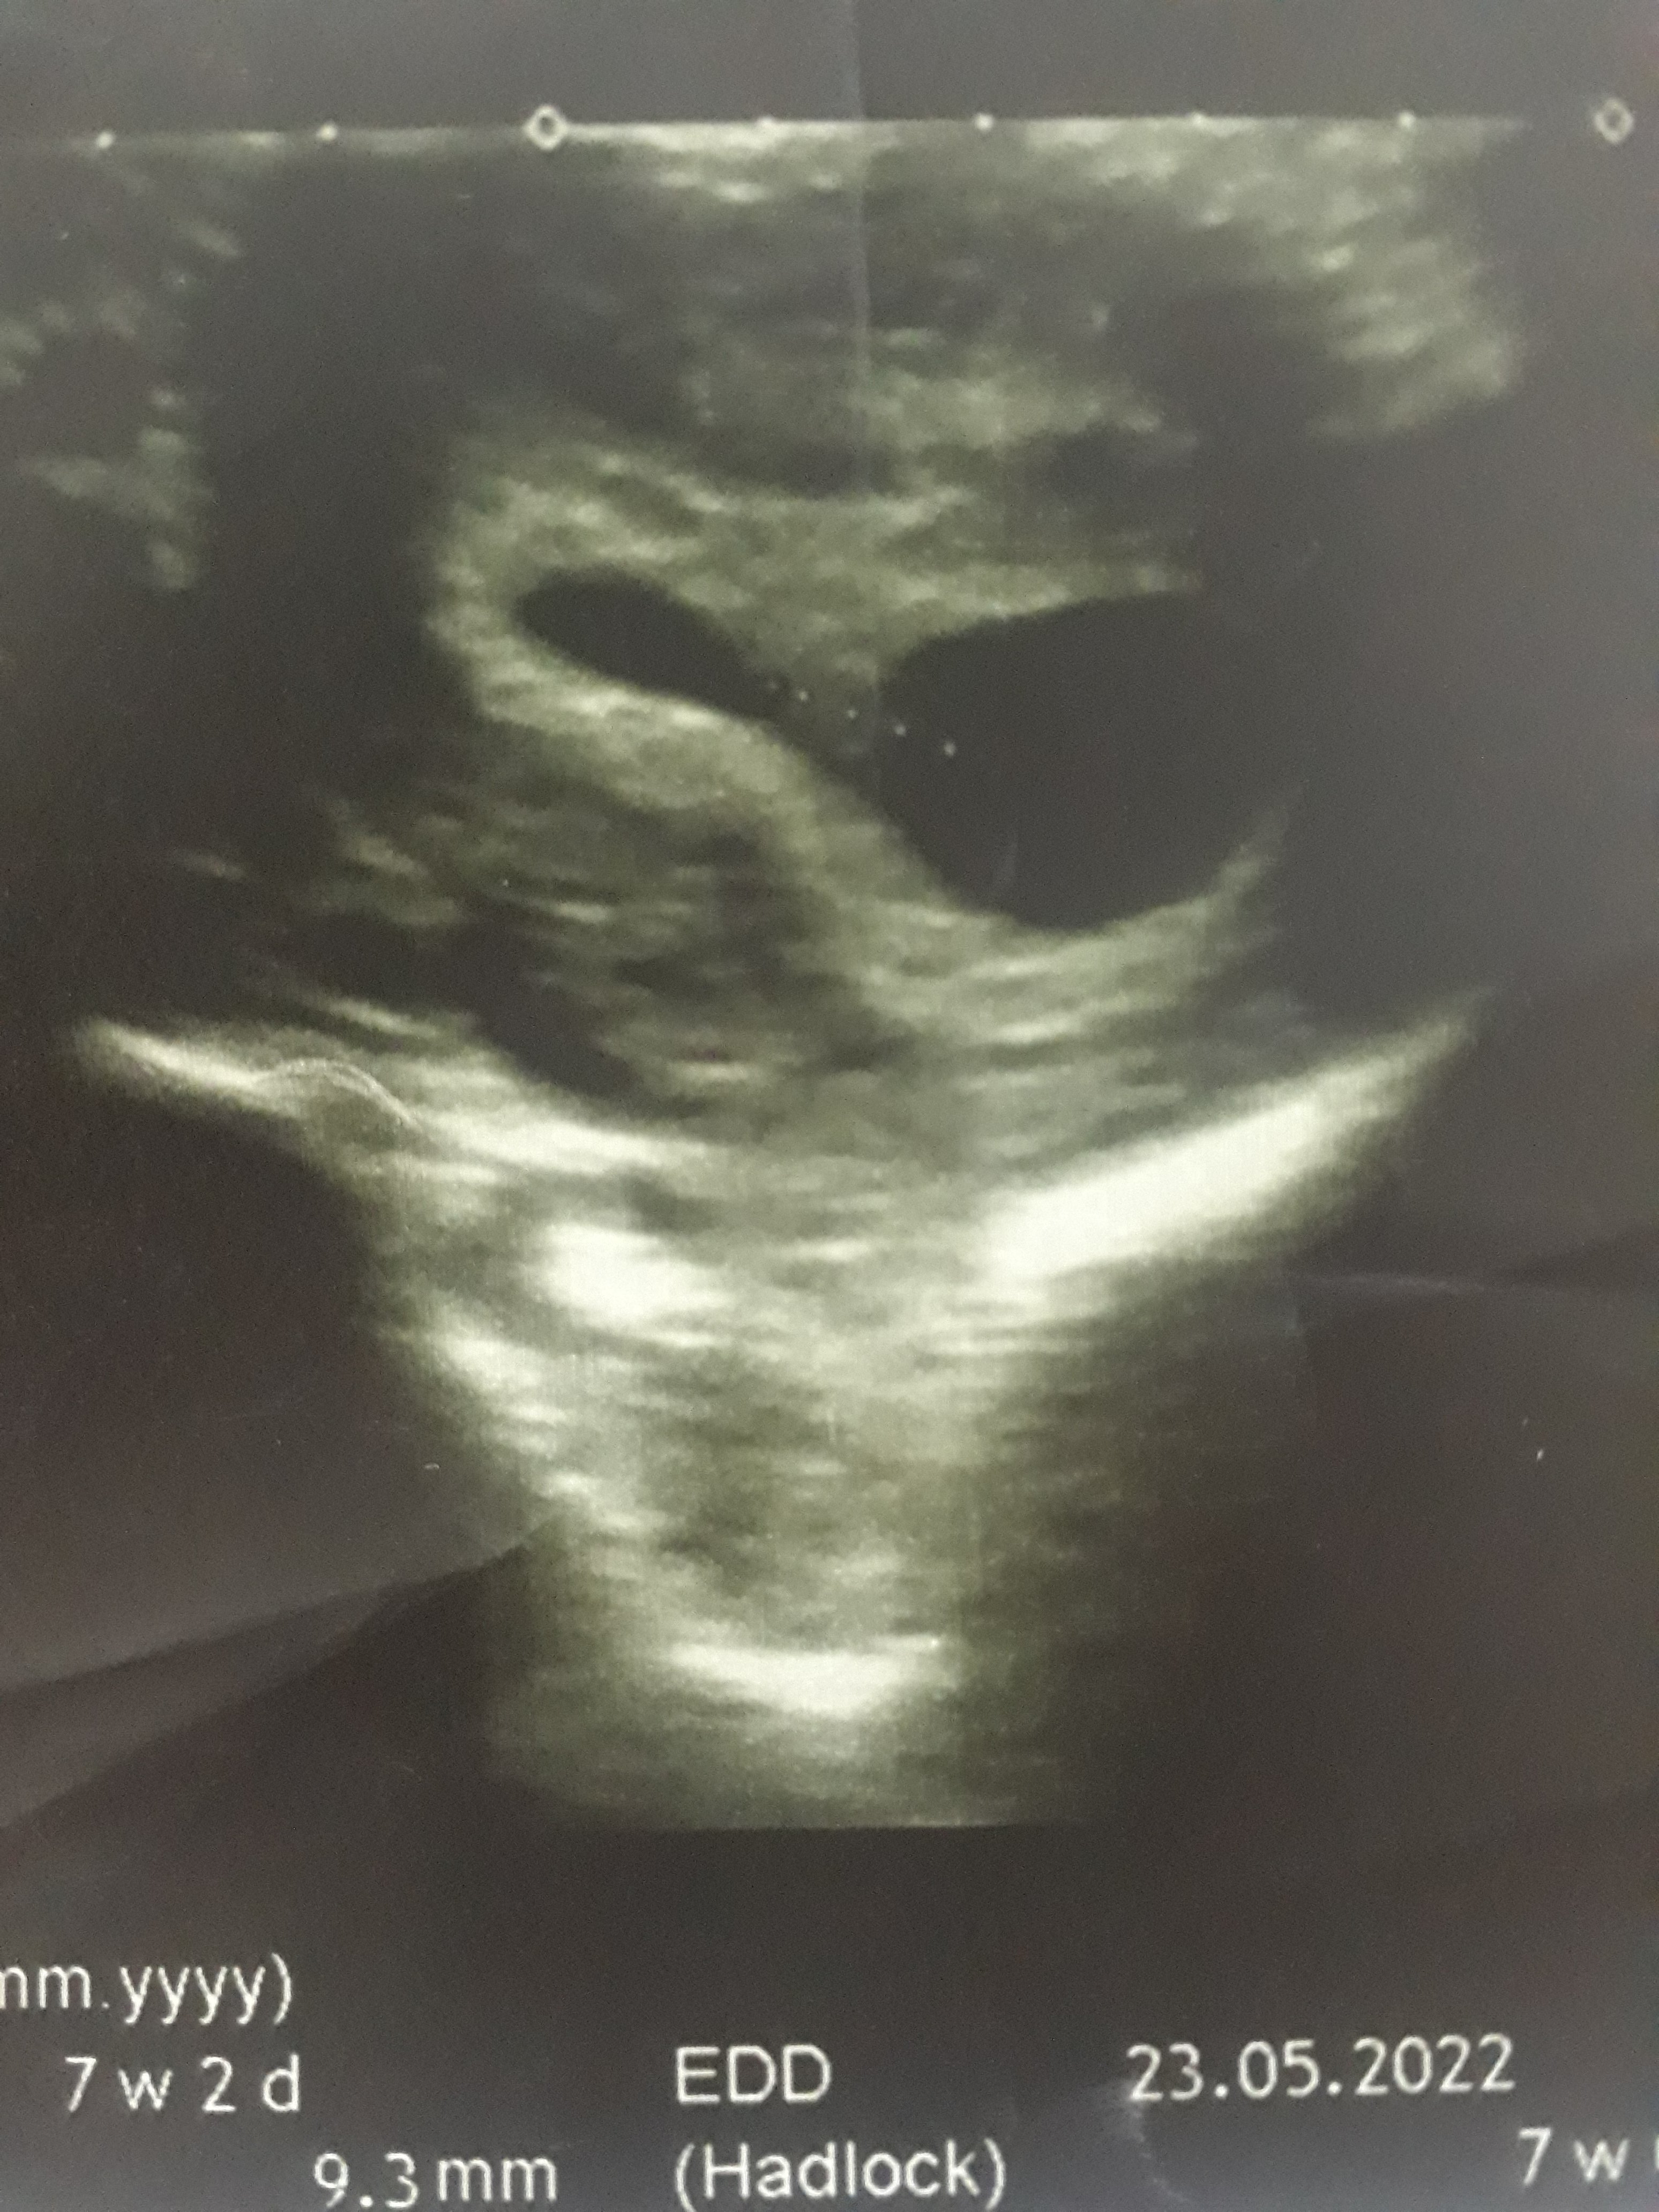

ultroson kağıdı

Konu Başlığı ultroson kağıdı

Ekli dosyalar

• 20211028_214147.jpg

1.6 MB · Görüntüleme: 179